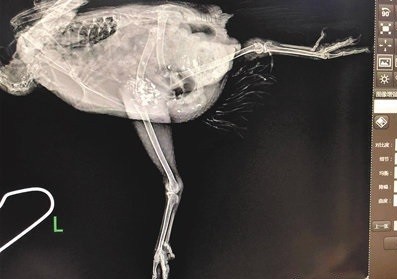

母雞受傷不把牠燉湯 他還花5000元帶去照X光

綜合媒體報導,中國重慶1名37歲男子陳輝,日前帶著寵物母雞「小黑黑」出門散步,結

果「小黑黑」的腳卡在水溝縫隙,陳輝將「小黑黑」的腳拔出後,但「小黑黑」回家後便

無法站立,連喜愛的食物也不吃,令他著急得不知該如何是好。

陳輝向鄰居詢問該如何是好,結果一堆人叫他燉湯,令他相當無奈,最後有人介紹動物醫

院給他,他才帶著「小黑黑」去醫院,接受儀器檢查,還拍了X光片,醫藥費1千多元人民

幣(約5千元台幣),情況逐漸好轉。